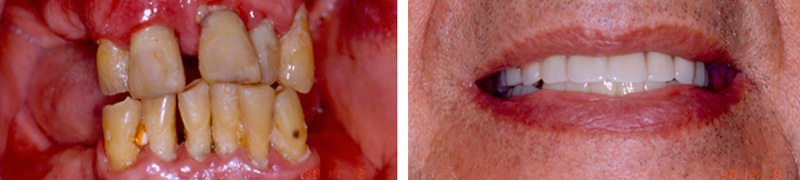

Στο οδοντιατρείο της ασχολείται με την Αισθητική και Επανορθωτική Οδοντιατρική και τα Οστεοενσωματούμενα Οδοντικά Εμφυτεύματα. Έχει εκτεταμένη εμπειρία στις οδοντικές προσθετικές αποκαταστάσεις και συστήματα οδοντικών εμφυτευμάτων, δίνοντας έμφαση πάντοτε στην αποκατάσταση της αισθητικής και της λειτουργικότητάς τους.

Στεφάνες επί εμφυτευμάτων

Εξαγωγή, άμεση εμφύτευση και άμεση φόρτιση

Επένθετες Οδοντοστοιχίες